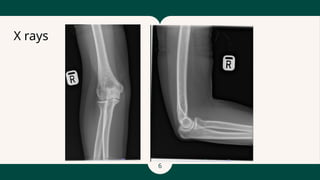

X Rays